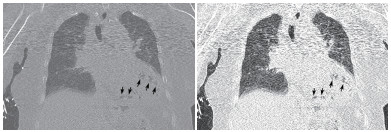

| 示气体影以左心室为著,外周分布为主,似累及心肌区域,部分心肌变薄(黑色箭头所示) 图 3 患者胸部CT冠状位影像 |

本例患者恶性肿瘤、糖尿病病史等使患者免疫功能低下,易合并重症急性感染。胸部CT显示左心室、室间隔及肺动脉根部区域见不规则条状、条片状低密度影,测量CT值提示为气体密度影。2016年Laiq等[1]曾报道因感染性心内膜炎致患者左心室内气体形成一例,患者血培养提示柠檬酸杆菌生长,最终患者发生急性心力衰竭,紧急二尖瓣置换术,术后乳头组织同样培养出柠檬酸杆菌,经抗感染治疗预后良好。2014年Alladina等[2]也曾报道一例因播散性肺克雷伯杆菌感染、产气,气体进入血液系统引起的脑空气栓塞。另外,临床工作中某些有创诊疗中,如深静脉置管、肺穿刺活检等也可能引起心脏空气栓塞[3-4]。但本例报道患者脑动脉、主动脉等大动脉系统未见明显气体影,说明患者左心室内气体不具有流动性。仔细观察胸部CT影像学表现,气体在左心室内主要沿室壁分布,部分心肌壁变薄,综合考虑为左室心内膜炎可能。左室内气体位于心内膜下,不在心腔内,故不具备游走性,这也就能解释为何患者其他动脉系统血管内不存在气体的原因。

本例患者存在重症急性感染,烦躁、皮肤湿冷、皮肤散在花斑,提示患者可能存在感染性休克,急性感染累及心内膜、心肌导致心内膜炎、心肌炎,细菌产气引起心内膜下气体形成。但遗憾的是,患者病情进展迅速,患者家属拒绝尸验,无法获得进一步临床资料。死亡原因推测可能为感染性休克,加之感染侵蚀患者心内膜,心肌使心肌变薄,最终引起心脏破裂或心内膜下气体破入心腔内引起空气栓塞而死亡。